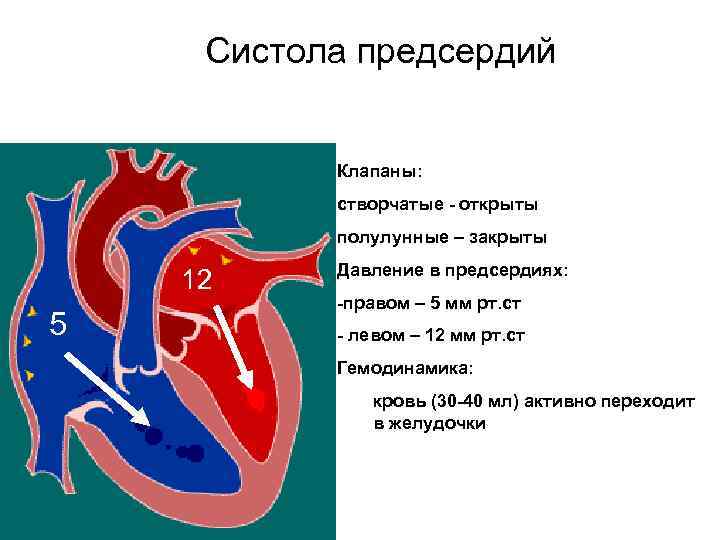

Систола предсердий Клапаны: створчатые - открыты полулунные – закрыты 12 5 Давление в предсердиях: -правом – 5 мм рт. ст - левом – 12 мм рт. ст Гемодинамика: кровь (30 -40 мл) активно переходит в желудочки

Систола предсердий Клапаны: створчатые - открыты полулунные – закрыты 12 5 Давление в предсердиях: -правом – 5 мм рт. ст - левом – 12 мм рт. ст Гемодинамика: кровь (30 -40 мл) активно переходит в желудочки